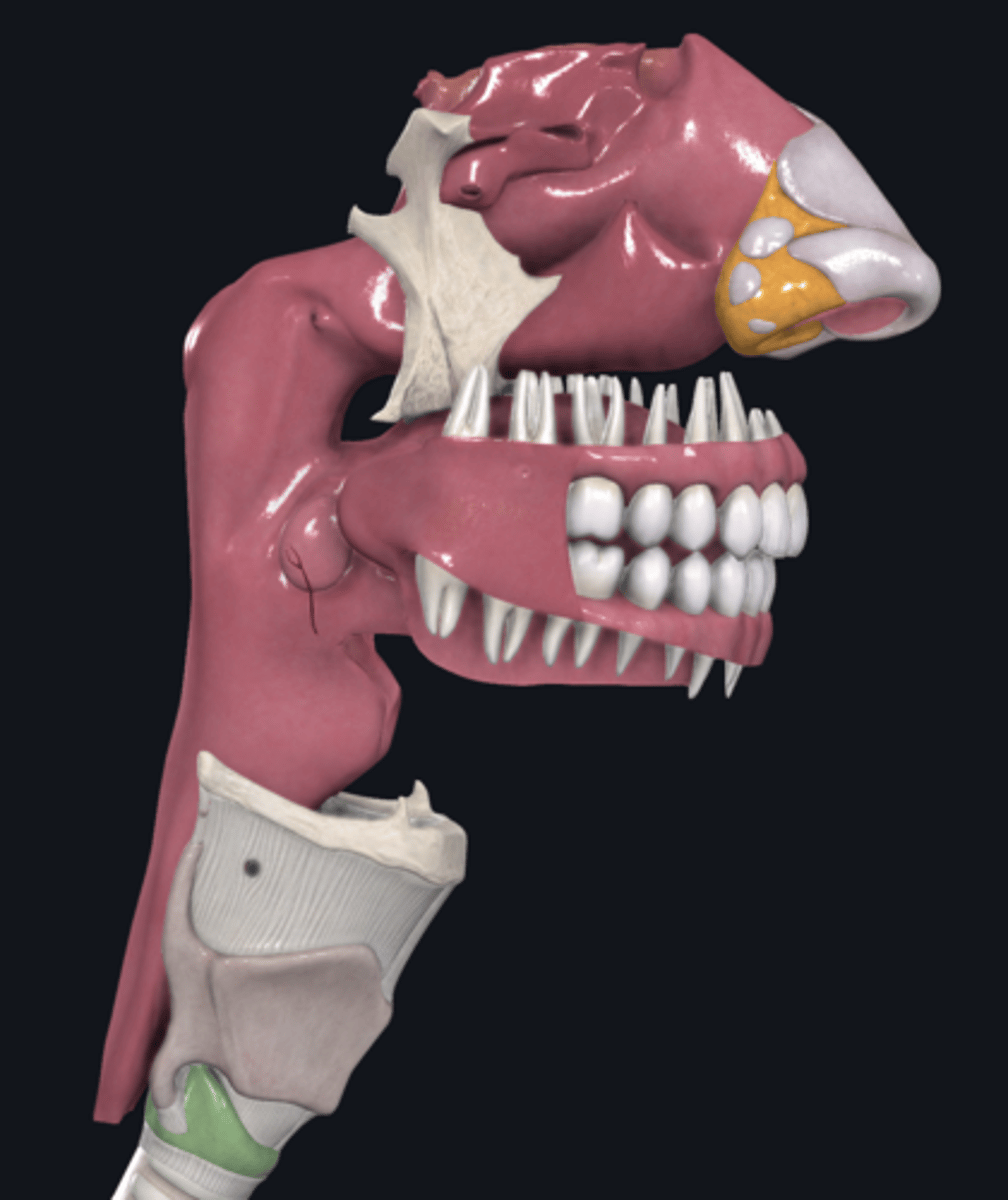

nose

external nares

vestibule

superior nasal conchae

Name A

middle nasal conchae

Name B

inferior nasal conchae

Name C

nasopharynx

name the circled region

oropharynx

name the circled region

epiglottis

palatine tonsils

pharyngeal tonsils

lingual tonsils

laryngopharynx

name the circled region

larynx

name the green portion

hyoid bone

name the green portion

thyroid cartilage

name the green portion

cricoid cartilage

name the green portion

arytenoid cartilage

name this cartilage

vocal ligament

name the ligament in this area

vocalis muscle

name this muscle